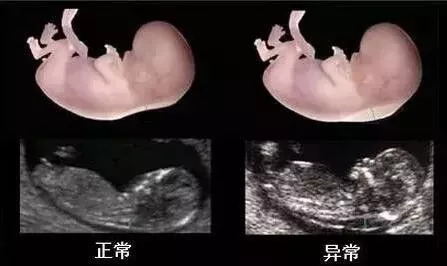

NT排畸检查是指,胎儿颈后部皮下组织内液集聚的厚度的检查。通过B超测定颈项透明层厚度,便于及早发现唐氏儿和先天性心脏病的胎儿,并及时予以干预。NT检查是筛查胎儿有没有先天愚型,是优生优育必要的检查。颈项透明层越厚,胎儿异常的概率越大。

NT增厚越明显,胎儿异常机会就越高,异常程度也会越严重。一般正常的NT厚度不能大于3mm,当大于3mm时约10%会发育为异常胎儿;当大于6mm时,这个异常程度会大大增加,约90%会发育成异常胎儿。NT检查就好比我们目前的安检工作,而NT增厚就好比安检过程中检查出的的异常人员,需要进一步排查。

当NT异常增厚时,就可能与胎儿染色体异常有关,比较常见的有2 1-三体、18-三体、13-三体综合征等等的,NT增厚能较好的评价胎儿罹患这些疾病的风险,也是早孕期间接诊断胎儿异常的一个标记.